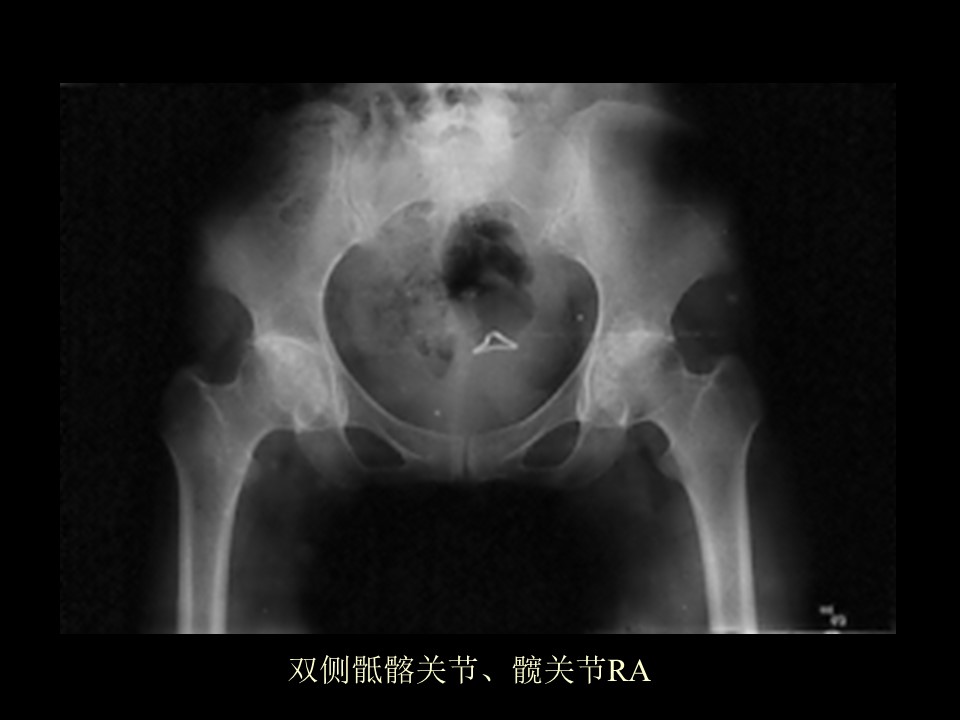

“类风湿性关节炎、强直性脊柱炎影像学诊断PPT” 的相关文章